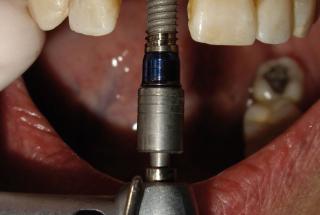

Clinical cases

MPI closely monitors clinical cases in the market to ensure their correct functioning and successful outcome.